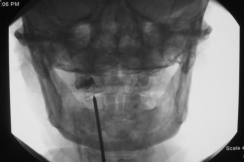

3.微创治疗:阻滞疗法(枕神经阻滞、C2背根神经节阻滞)、射频治疗(C2背根神经节脉冲射频、C3脊神经后支射频、枕大小神经射频)和电刺激治疗(周围电刺激术、脊髓电刺激术),听到微创治疗不要紧张,都是局部麻醉,在颈部打个小针就可以了。